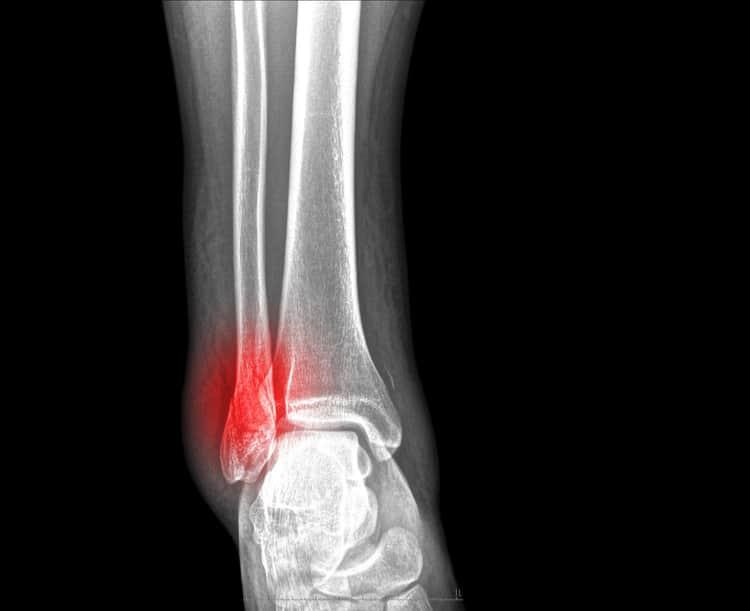

Xương chày là một trong hai xương lớn ở cẳng chân, có thể nứt hoặc thậm chí gãy khi có một lực lớn trực tiếp tác động lên. Đây là một trong những đoạn xương thường bị gãy nhất trong cơ thể.

Xét nghiệm như X-quang và các chẩn đoán hình ảnh như chụp CT được khuyến khích. X-quang giúp xác nhận gãy xương và cũng tìm hiểu đầu gối hoặc khớp mắt cá chân có bị ảnh hưởng bởi gãy xương không.

Sau khi đọc hình chụp X-quang, nếu bác sĩ nghi ngờ đầu gối hoặc mắt cá chân bị ảnh hưởng, bạn sẽ cần chụp CT.